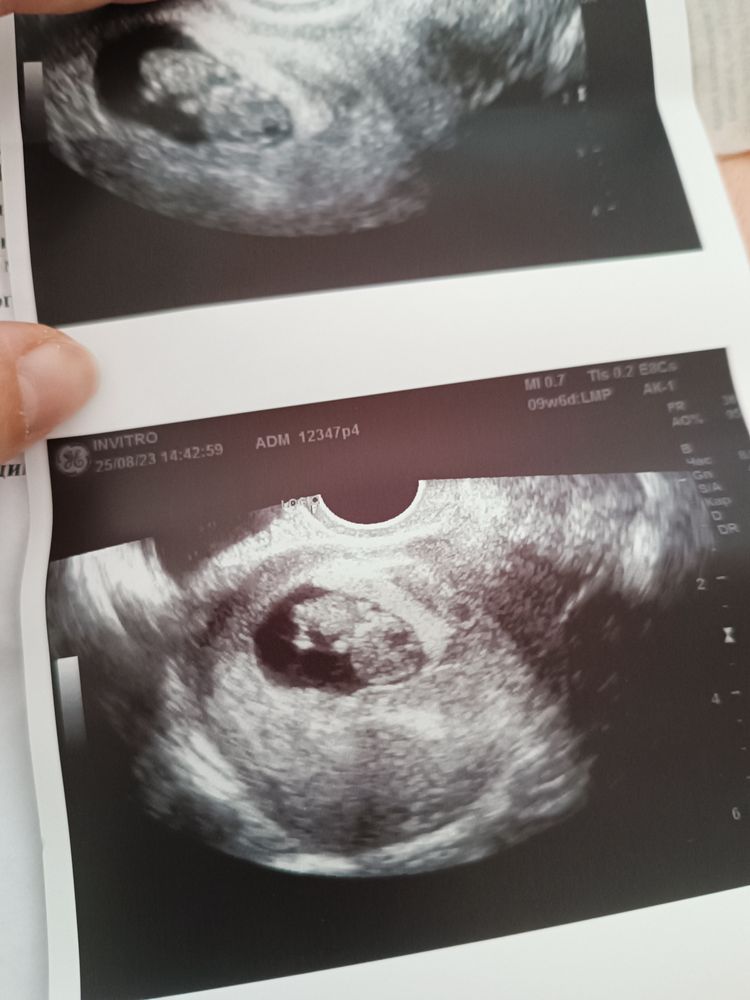

Была на УЗИ. Узист сказал что всё отлично. Но в заключении указано что ПЯ 25 мм, а ктр 23 мм. Это же катастрофически мало! Боюсь что ему мало места(((((( Хотя по фото УЗИ место ещё есть. Так же есть гипертонус по задней стенке. Возможно из за него ещё так сплющило.Что думаете?

Екатерина, по фото узи, кажется что яйцо нормальное. Не переживайте раньше времени